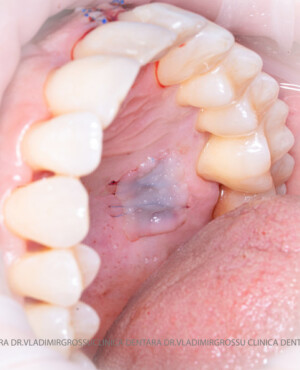

Un element esențial în procedura de aditie osoasă este utilizarea membranelor biologice, care izolează materialul osos de țesuturile moi (gingie) pe durata procesului de vindecare. Cele mai recomandate sunt membranele resorbabile din colagen sau pericard.

Procesul de refacere osoasă este complex, însă, simplificat, se bazează pe faptul că osul adăugat se integrează treptat, fiind înlocuit parțial cu os natural, oferind astfel suportul necesar implantului.